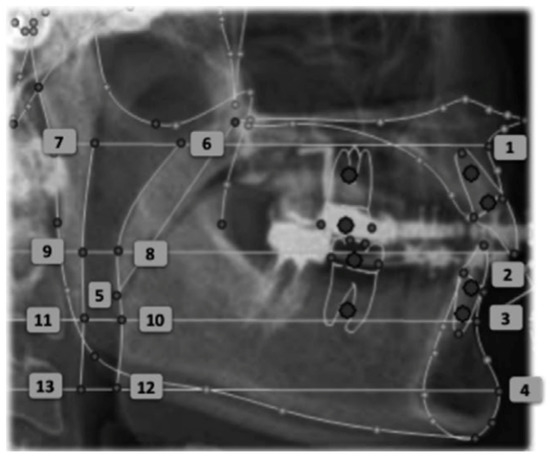

In all patients, two lateral cephalograms were taken, one before starting treatment (T0) and the other after 1 year of treatment (T1). In the final teleradiography (T1) the patients had the MAD placed intra-orally (Figure 2). Moreover, during the evaluation of the results, all patients underwent cardiorespiratory study polysomnography (AASM level III).

Figure 2. Teleradiography without the device in place (A) and teleradiography one year after treatment with the device in place (B). The orange line measures 10 mm.